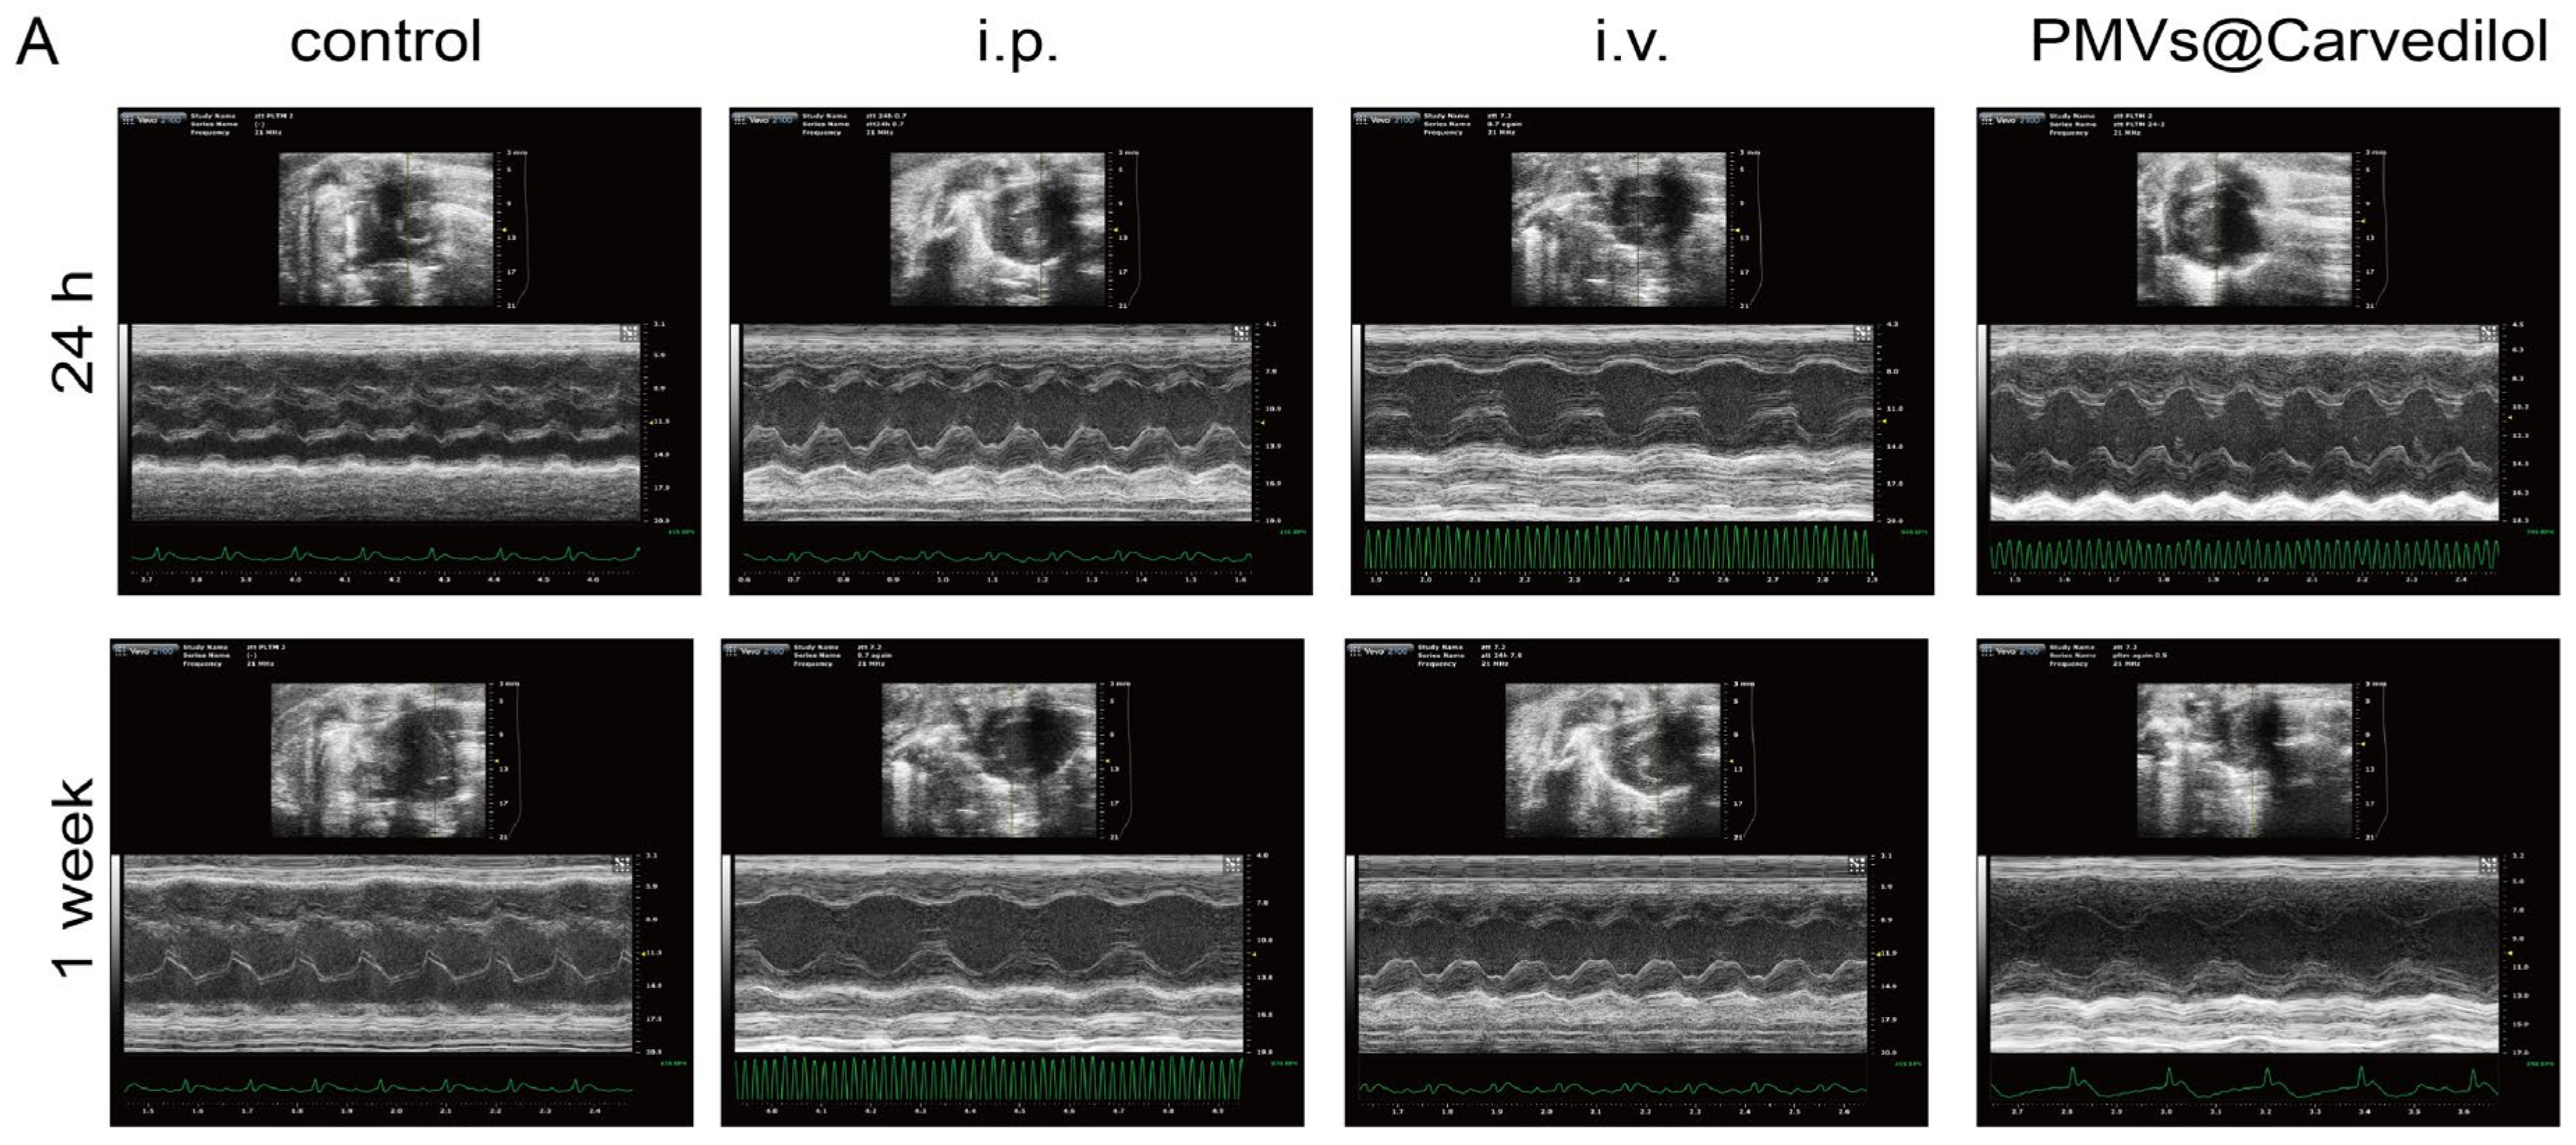

3.4. Compared with Other Administration Methods, PMVs@Carvedilol Can Better Reduce Infarct Size, Reduce Myocardial Cell Apoptosis, and Improve Cardiac Function